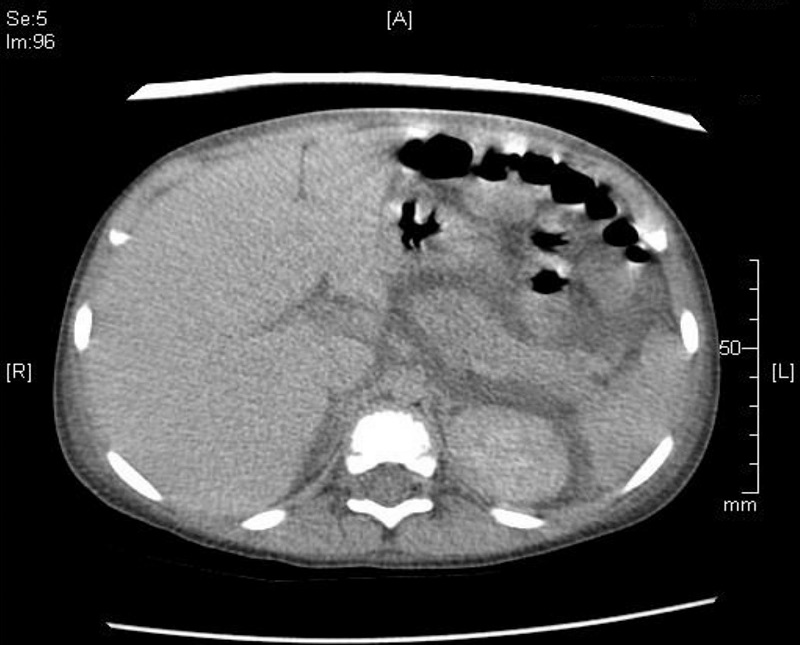

TC abdominal: páncreas aumentado de tamaño, sin áreas de necrosis ni imágenes quísticas en el parénquima. Líquido libre en retroperitoneo y derrame pleural izquierdo. Riñones de tamaño normal y aspecto globuloso.

Se repite la ecografía abdominal, con aumento de líquido libre, persistiendo aumento del tamaño del páncreas y ecoestructura heterogénea. Se realiza una tomografía computarizada (TC) abdominal para confirmación diagnóstica.